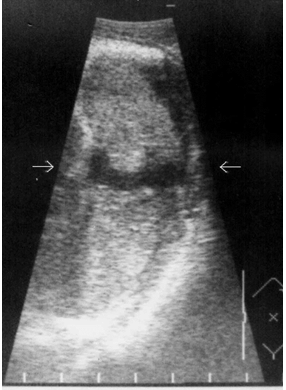

Ушибы селезенки сопровождаются интерстициальным отеком и геморрагическим пропитыванием тканей. Прямыми эхографическими признаками в первые 3–5 часов после травмы являются снижение эхогенности паренхимы и четкости контура органа, а также «разреженность» эхоструктуры паренхимы. Геморрагическое пропитывание паренхимы манифестировало наличием гиперэхогенных зон с нечеткими размытыми контурами в области повреждения (рис. 1). Характерно увеличение размеров всей селезенки или преимущественно поврежденного сегмента с нарушением ее конфигурации. Результаты цветового допплеровского картирования свидетельствуют о снижении кровотока, степень которого коррелирует с выраженностью эхографических проявлений отека паренхимы.

Рис. 1. Ушиб селезенки. Зона геморрагического пропитывания указана стрелками.